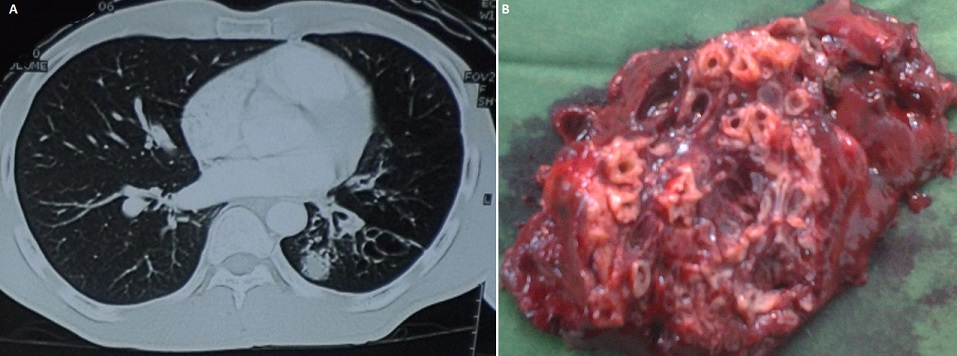

The bronchial dilations also called bronchiectasis are permanent and irreversible increase in the bronchial tubes. They can be extended or localized especially in pulmonary tuberculosis sequelae. This affection is serious, because it is at the origin of an embarrassing obstructive pulmonary disease, leading to social discomfort and preferentially in Côte d'Ivoire, it affects young subjects between 30 and 40 years old and former tuberculous. The place of surgery is still debated. Mr Coulibaly is 30 years old, hospitalized in the Thoracic Surgery Department of BouakeTeaching Hospital for pulmonary tuberculosis sequelae type symptomatic left lower bronchiectasis lobe and well localized (A). After a satisfactory preoperative evaluation, we performed a left lower lobectomy on this patient. Transection in the third world of the bronchial lower lobe resected reveals multiple tubular dilations with thickened wall containing purulent secretions (B). The specimen was sent to the pathology laboratory for confirmation of tuberculosis sequelae.